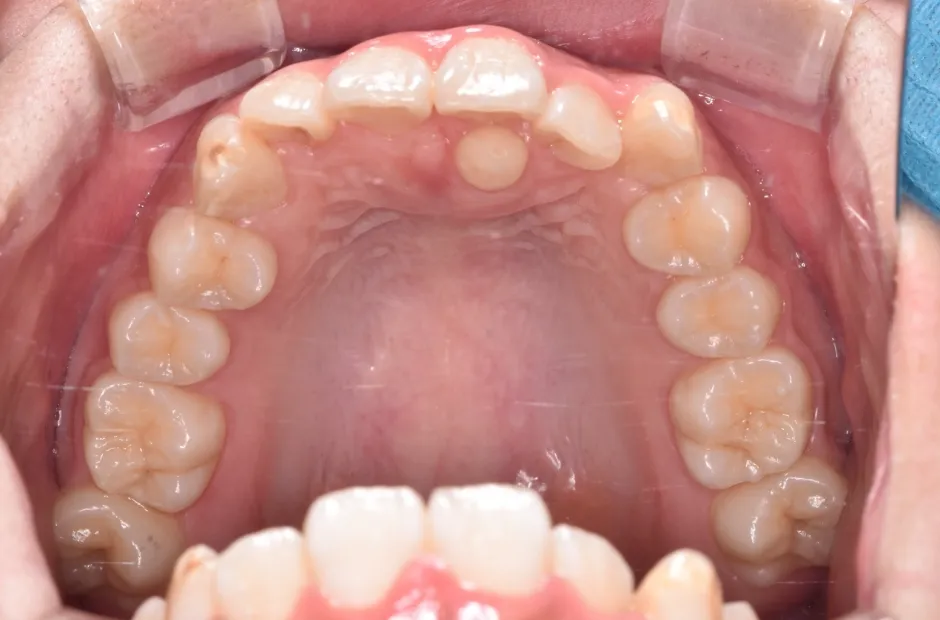

叢生

| 診断名・主訴 | 叢生 |

|---|---|

| 年齢・性別 | 43歳・女性 |

| 治療期間・回数 | 2年7か月 27回 |

| 治療に用いた主な装置 | 舌側矯正 |

| 抜歯部位 | 両顎4,4 |

| 治療費 | 100万円(税抜) |

| リスク・副作用 | 装置による違和感・疼痛・歯肉退縮・歯根吸収・虫歯のリスクなど |